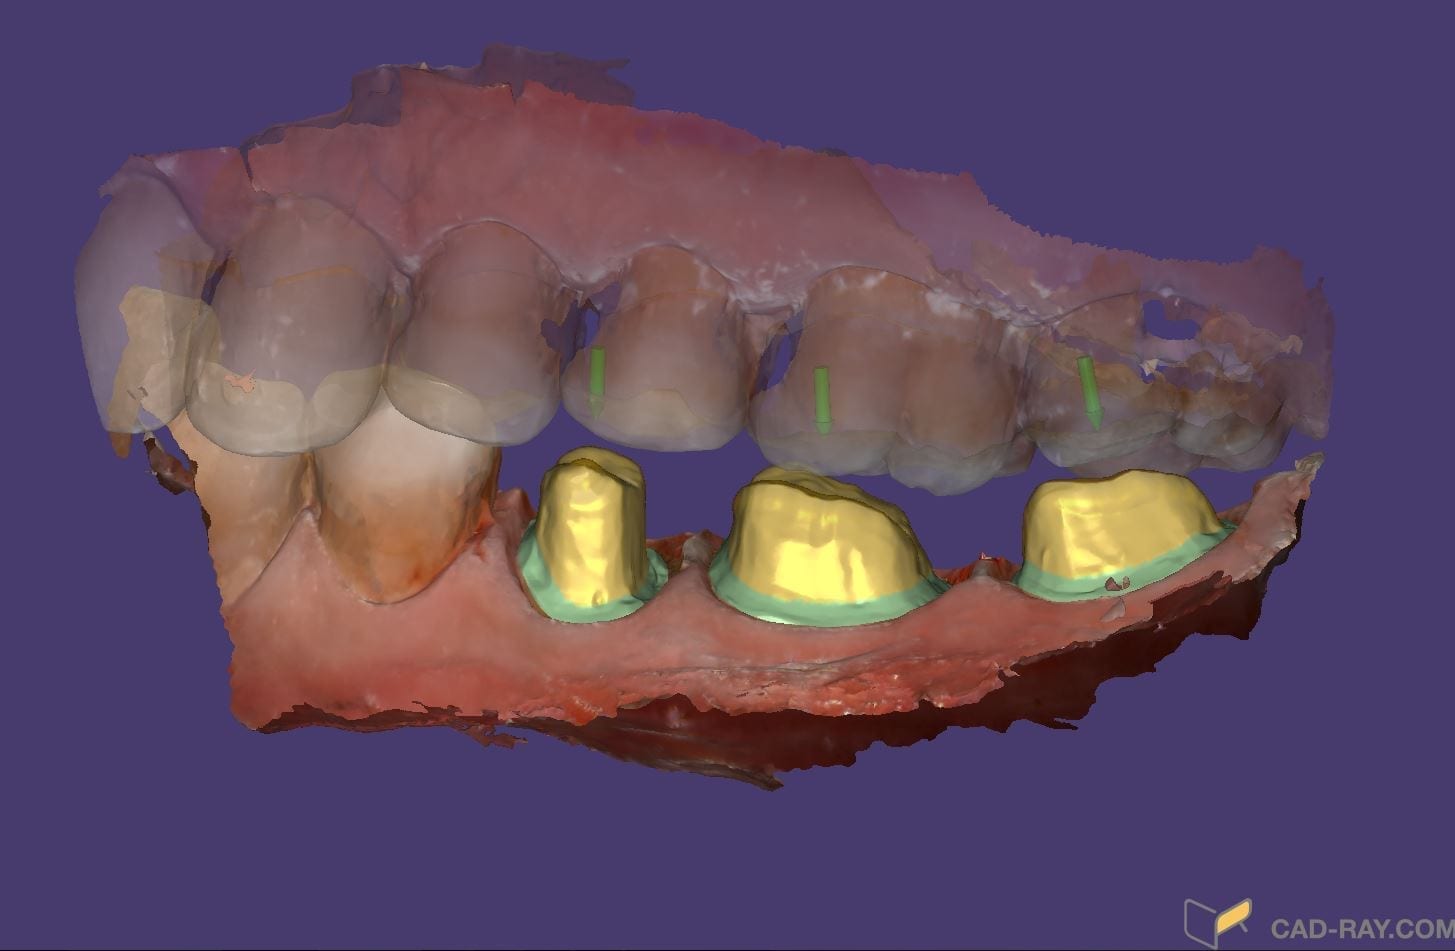

Bridge Replacement with the Medit i500 Using Copy Mode of the Pre-op, White Light for Red Tissue, Blue Light for Tooth Structure, and Segmented Model Building

February 4, 2019This failing three unit fixed partial denture was replaced with the Medit i500 and the CAD-Ray Design Software. While the patient was getting numb, a physical quadrant impression was made […]